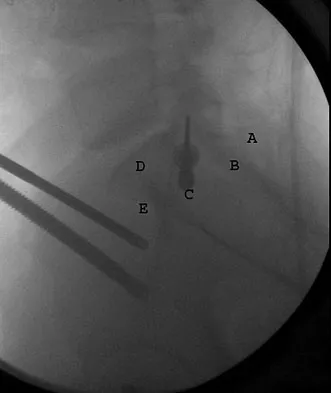

A 7-year-old patient has had a painless limp for several months. Examination reveals pain and spasm with internal rotation, and abduction is limited to 10 degrees on the involved side. Management consists of 1 week of bed rest and traction, followed by an arthrogram. A maximum abduction/internal rotation view is shown in Figure 40a, and abduction and adduction views are shown in Figures 40b and 40c. The studies are most consistent with

Explanation

The radiographs show classic hinge abduction. The diagnostic feature is the failure of the lateral epiphysis to slide under the acetabular edge with abduction, and the abduction view shows medial dye pooling because of distraction of the hip joint. Persistent hinge abduction has been shown to prevent femoral head remodeling by the acetabulum. Radiographic changes are characteristic of severe involvement with Legg-Calve-Perthes disease.The Catterall classification cannot be well applied without a lateral radiograph, but this degree of involvement would likely be considered a grade III or IV. Because the lateral pillar is involved, this condition would be classified as type C using the Herring lateral pillar classification scheme.